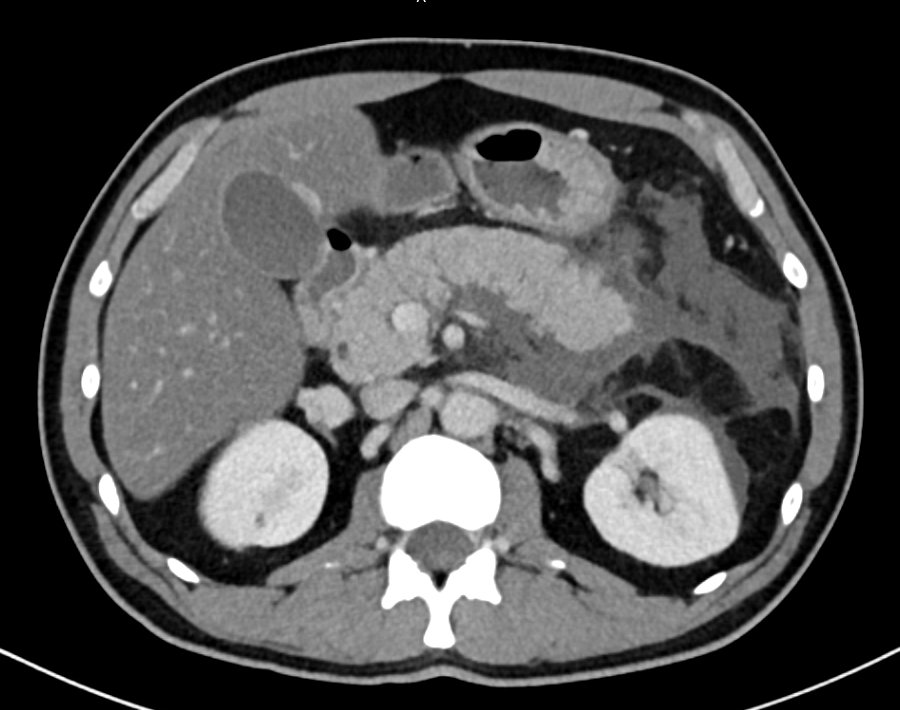

@IhabFathiSulima Acute pancreatitis

CT finding : peripancreatic fat stranding